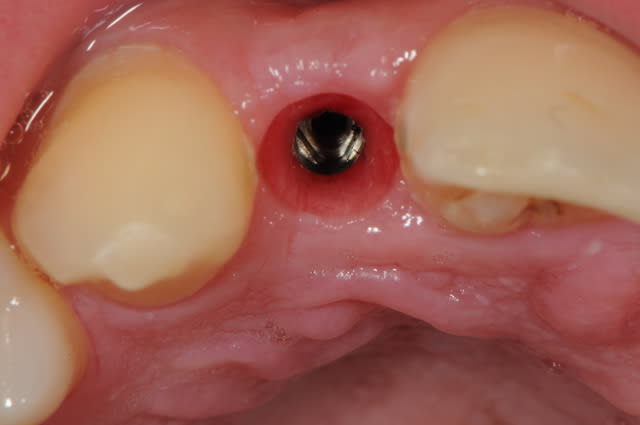

01/09/2010 à 16h28

-cicatrisation de la première vis de cica,

-diamètre plus gros pour la vis de cica

- pilier pour la provisoire

- provisoire moule ION

- ajustage

- polissage soigneux

la suite tout à l'heure, ça sonne à la porte...